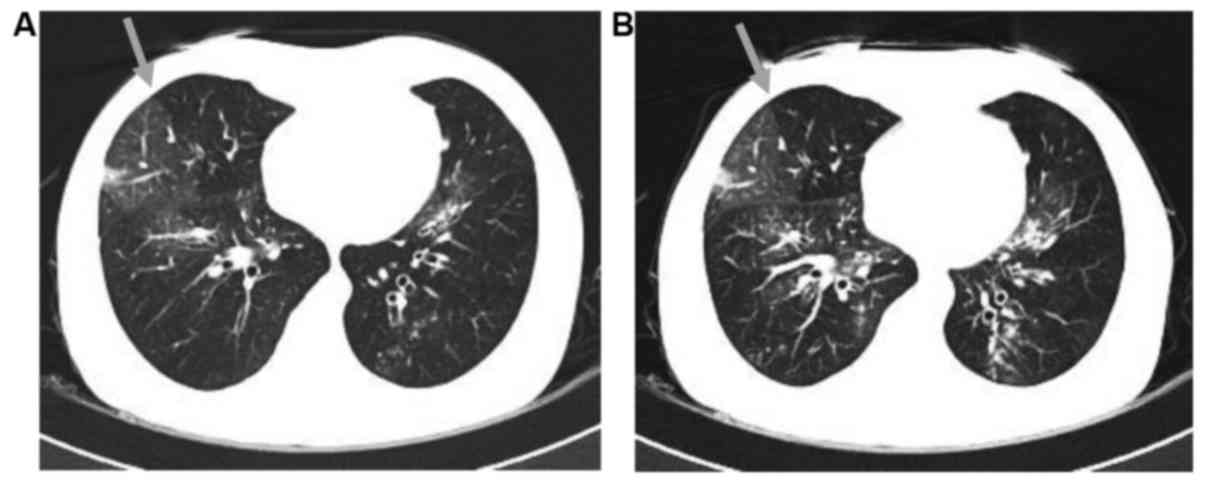

However, 1 month after the release from hospital the patient developed dyspnea and a productive cough. The patient was then presented to Zhongshan Hospital, Fudan University (Shanghai, China). Blood gas examination revealed hypoxemia [partial pressure of O2, 73 mmHg (normal range, 80–100 mmHg); partial pressure of CO2, 39 mmHg (normal range, 35–45 mmHg)], and pulmonary function tests demonstrated severe obstruction, with a forced expiratory volume in 1 sec (FEV1) of 21.5%, FEV1/forced vital capacity (FVC) of 46.6%, and a mild diffusion defect [FEV1, 0.45 liters (15% of predicted value); FVC, 42% of predicted value]. The single-breath diffusing capacity of the lungs for CO2CO (DLCO) was 12.5 ml/mmHg/min (68% of the predicted value), while the DLCO divided by the alveolar volume was 5.67 ml/mmHg/min (123% of the predicted value). Furthermore, bronchodilation examination indicated non-reversible obstruction. A chest high-resolution computed tomography (HRCT) scan demonstrated central bronchiectasis (Fig. 1). Subsequently, a chest CT with inspiratory and expiratory images was further conducted to evaluate these findings. In the inspiratory image (Fig. 2A), a heterogeneous opacity was visible in a mosaic or patchy pattern. The expiratory image (Fig. 2B) revealed an area of trapped air in the lung, showing an attenuated intensity compared with the adjacent normal lung. These results, including a respiratory function test and radiological examination, were highly suggestive of bronchiolitis obliterans (BO).

Figure 2.

(A) Inspiratory CT scan demonstrating mosaic attenuation at the upper lobes of the two lungs. An area of decreased attenuation in the right lobe is demarcated by the gray arrow. (B) Expiratory CT, performed at approximately the same level as the inspiratory image. The area of decreased attenuation in the right lobe remained lucent on expiration (gray arrow). CT, computed tomography.